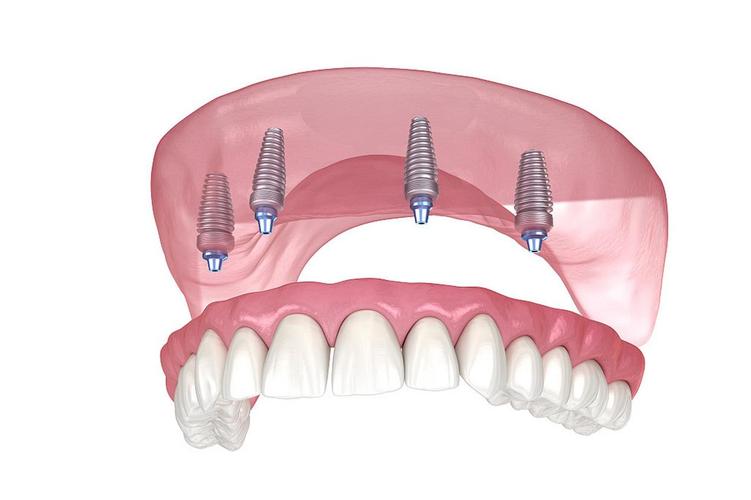

是以选择四颗种植体还是六颗种植体,关键取决于骨量状况以及咀嚼力方面的需求。All-on-4技术于后牙区域运用倾斜植入的方式,避免上颌窦亦或是下颌神经管,适宜骨量呈现轻度萎缩情形的患者。然而四颗种植体分散咬合力这一能力较为弱些,要是喜爱食用硬物亦或是存在夜间磨牙的情况,那么可能增加植体所承受的负荷。All-on-6在磨牙区会额外多植入两颗植体,受力更为均匀,适合骨量充裕或者对咀嚼效率有着较高要求的人群。临床所获取的数据表明,六颗方案长期的成功率略微高一点,但是手术的复杂程度以及费用也会相应地有所增加。

在生物力学层面来看,对于半口修复来讲的话,起码得要有4颗种植体方能稳定地去支撑连桥牙冠。要是骨量极其差并且没办法进行植骨的情况,能够采用穿颧种植这个方式,或者是选择2颗植体加上两端延伸的那种“悬臂桥”,不过后面这种方式失败的风险是比较高的,仅仅是当作一种妥协的方案。实际上标准答案是这样的:正常的状况下种植4颗,要是追求更加耐用的状况就选择6颗。需要注意的是,种植体的数量并非是越多就越好的,数量过多的话会损伤健康的骨组织,而且会增加清洁的难度。医生会借助CBCT三维测量骨的高度、厚度以及神经所在的位置,从而精确地规划植入的位点。